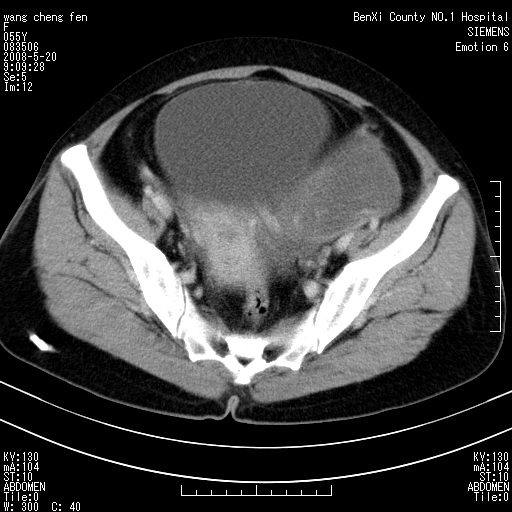

女、绝经后阴道流血3个月

左侧附件区可见一囊性占位,边缘清楚,内可见不规则形软组织影 ce:囊壁及内部可见强化 考虑 卵巢囊腺瘤

左侧附件区巨大囊实性病灶,边缘光整,病灶囊壁较厚,增强示囊壁及实性部分明显强化,强化呈度与宫体实质大致相同,宫腔积液征像,未见盆腔积液等其他异常,考虑左侧卵巢囊腺癌,不除外囊腺瘤及浆膜下肌瘤坏死

左侧附件区巨大囊实性病灶,边缘光整,病灶囊壁较厚,增强示囊壁及实性部分明显强化,强化呈度与宫体实质大致相同,宫腔积液征像,未见盆腔积液等其他异常。绝经后阴道流血3个月,结合病史左侧卵巢囊腺癌首先考虑,宫腔扩大不除外累及。期待结果。

支持浆膜下子宫肌瘤.之前由于网络原因未看全图片,现在重看,宫颈见一类圆形低密度影,增强轻度强化,低于肌层强化,宫腔扩大,考虑宫颈癌伴宫腔积液可能性大.